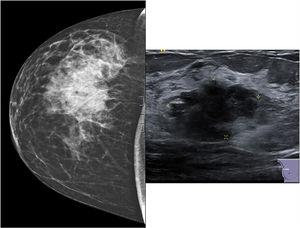

Mujer de 64 años, sin antecedentes de interés, que consultó por un nódulo en mama derecha de varios meses de evolución sin otra sintomatología. En el estudio mamográfico se evidenciaba una tumoración con nódulos satélites, de 44mm x 22mm, en el cuadrante superoexterno de la mama derecha. En el estudio ecográfico se apreciaba una masa de morfología y márgenes irregulares, hipoecogénica, asociada a múltiples nódulos satélites, sin adenopatías axilares sospechosas (fig. 1). En la biopsia ecoguiada con aguja gruesa se informó de carcinoma neuroendocrino con receptores hormonales positivos y herceptest negativo. En el estudio inmunohistoquímico, la tumoración fue positiva, en su totalidad, para marcadores neuroendocrinos (sinaptofisina y cromogranina) (fig. 2). La negatividad para TTF1, CK7, CK20 y CDx2 descartaba un origen pulmonar o digestivo y la positividad para receptores hormonales hizo sospechar de un origen primario de mama. Tras realizar PET-TAC, que fue normal, se indicó tratamiento quirúrgico con mastectomía por el tamaño tumoral, y biopsia selectiva del ganglio centinela, aislando 2 ganglios que fueron negativos (estadio IIa). La histología definitiva informaba de un carcinoma neuroendocrino pobremente diferenciado de 45mm con invasión linfovascular. En la inmunohistoquímica definitiva presentaba positividad para cromogranina, sinaptofisina, mamoglobina y GCDFP-15 y fue negativo para CD56, lo que orientó más a carcinoma neuroendocrino que a carcinoma ductal infiltrante con diferenciación neuroendocrina. La paciente recibió tratamiento con antraciclinas y taxanos de forma adyuvante, estando actualmente y tras 6 meses de revisión, libre de enfermedad.